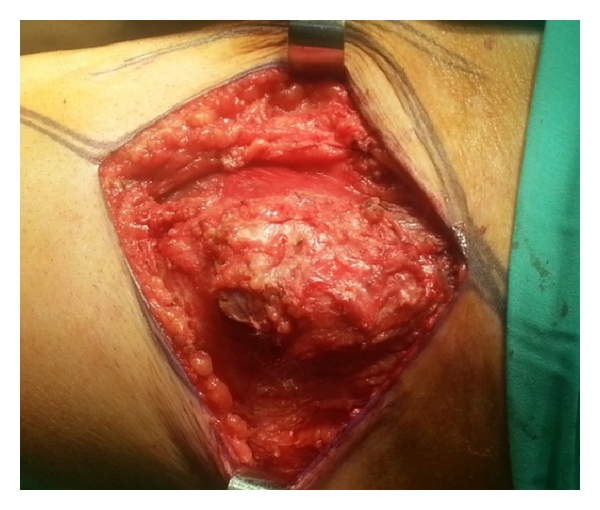

The patient underwent surgical resection of the lesion after induction of general anesthesia. The mass involved only the muscular plane of the sartorius, 10 cm approximately from the origin without evident contact with the tendon or adjacent muscle. A marginal excision of the lesion was performed. Macroscopically, it was an 8 × 4 × 4 cm lesion with smooth margins and the cross-section was white and shiny (Figures 1 and 2). The postoperative period was uneventful. The pathology of the lesion reported a 9 × 4 × 3,9 cm skeletal muscle with a solid lesion of a maximal diameter of 7,2 cm. The skeletal muscle was infiltrated from a malignant lesion compatible with a high grade urothelial carcinoma positive to the CK7 marker and negative to the CK20 (Figure 3). The marker of cellular proliferation Ki67 was 40% positive. The patient subsequently received systematic chemotherapy with gemcitabine and cisplatin (6 cycles) and was subjected to radiotherapy at the site of the excision of the skeletal muscle metastasis and that of the cystectomy. The patient 7 months after the excision of the muscle metastasis in the left thigh is still alive and with a good performance status with a negative imaging follow-up.